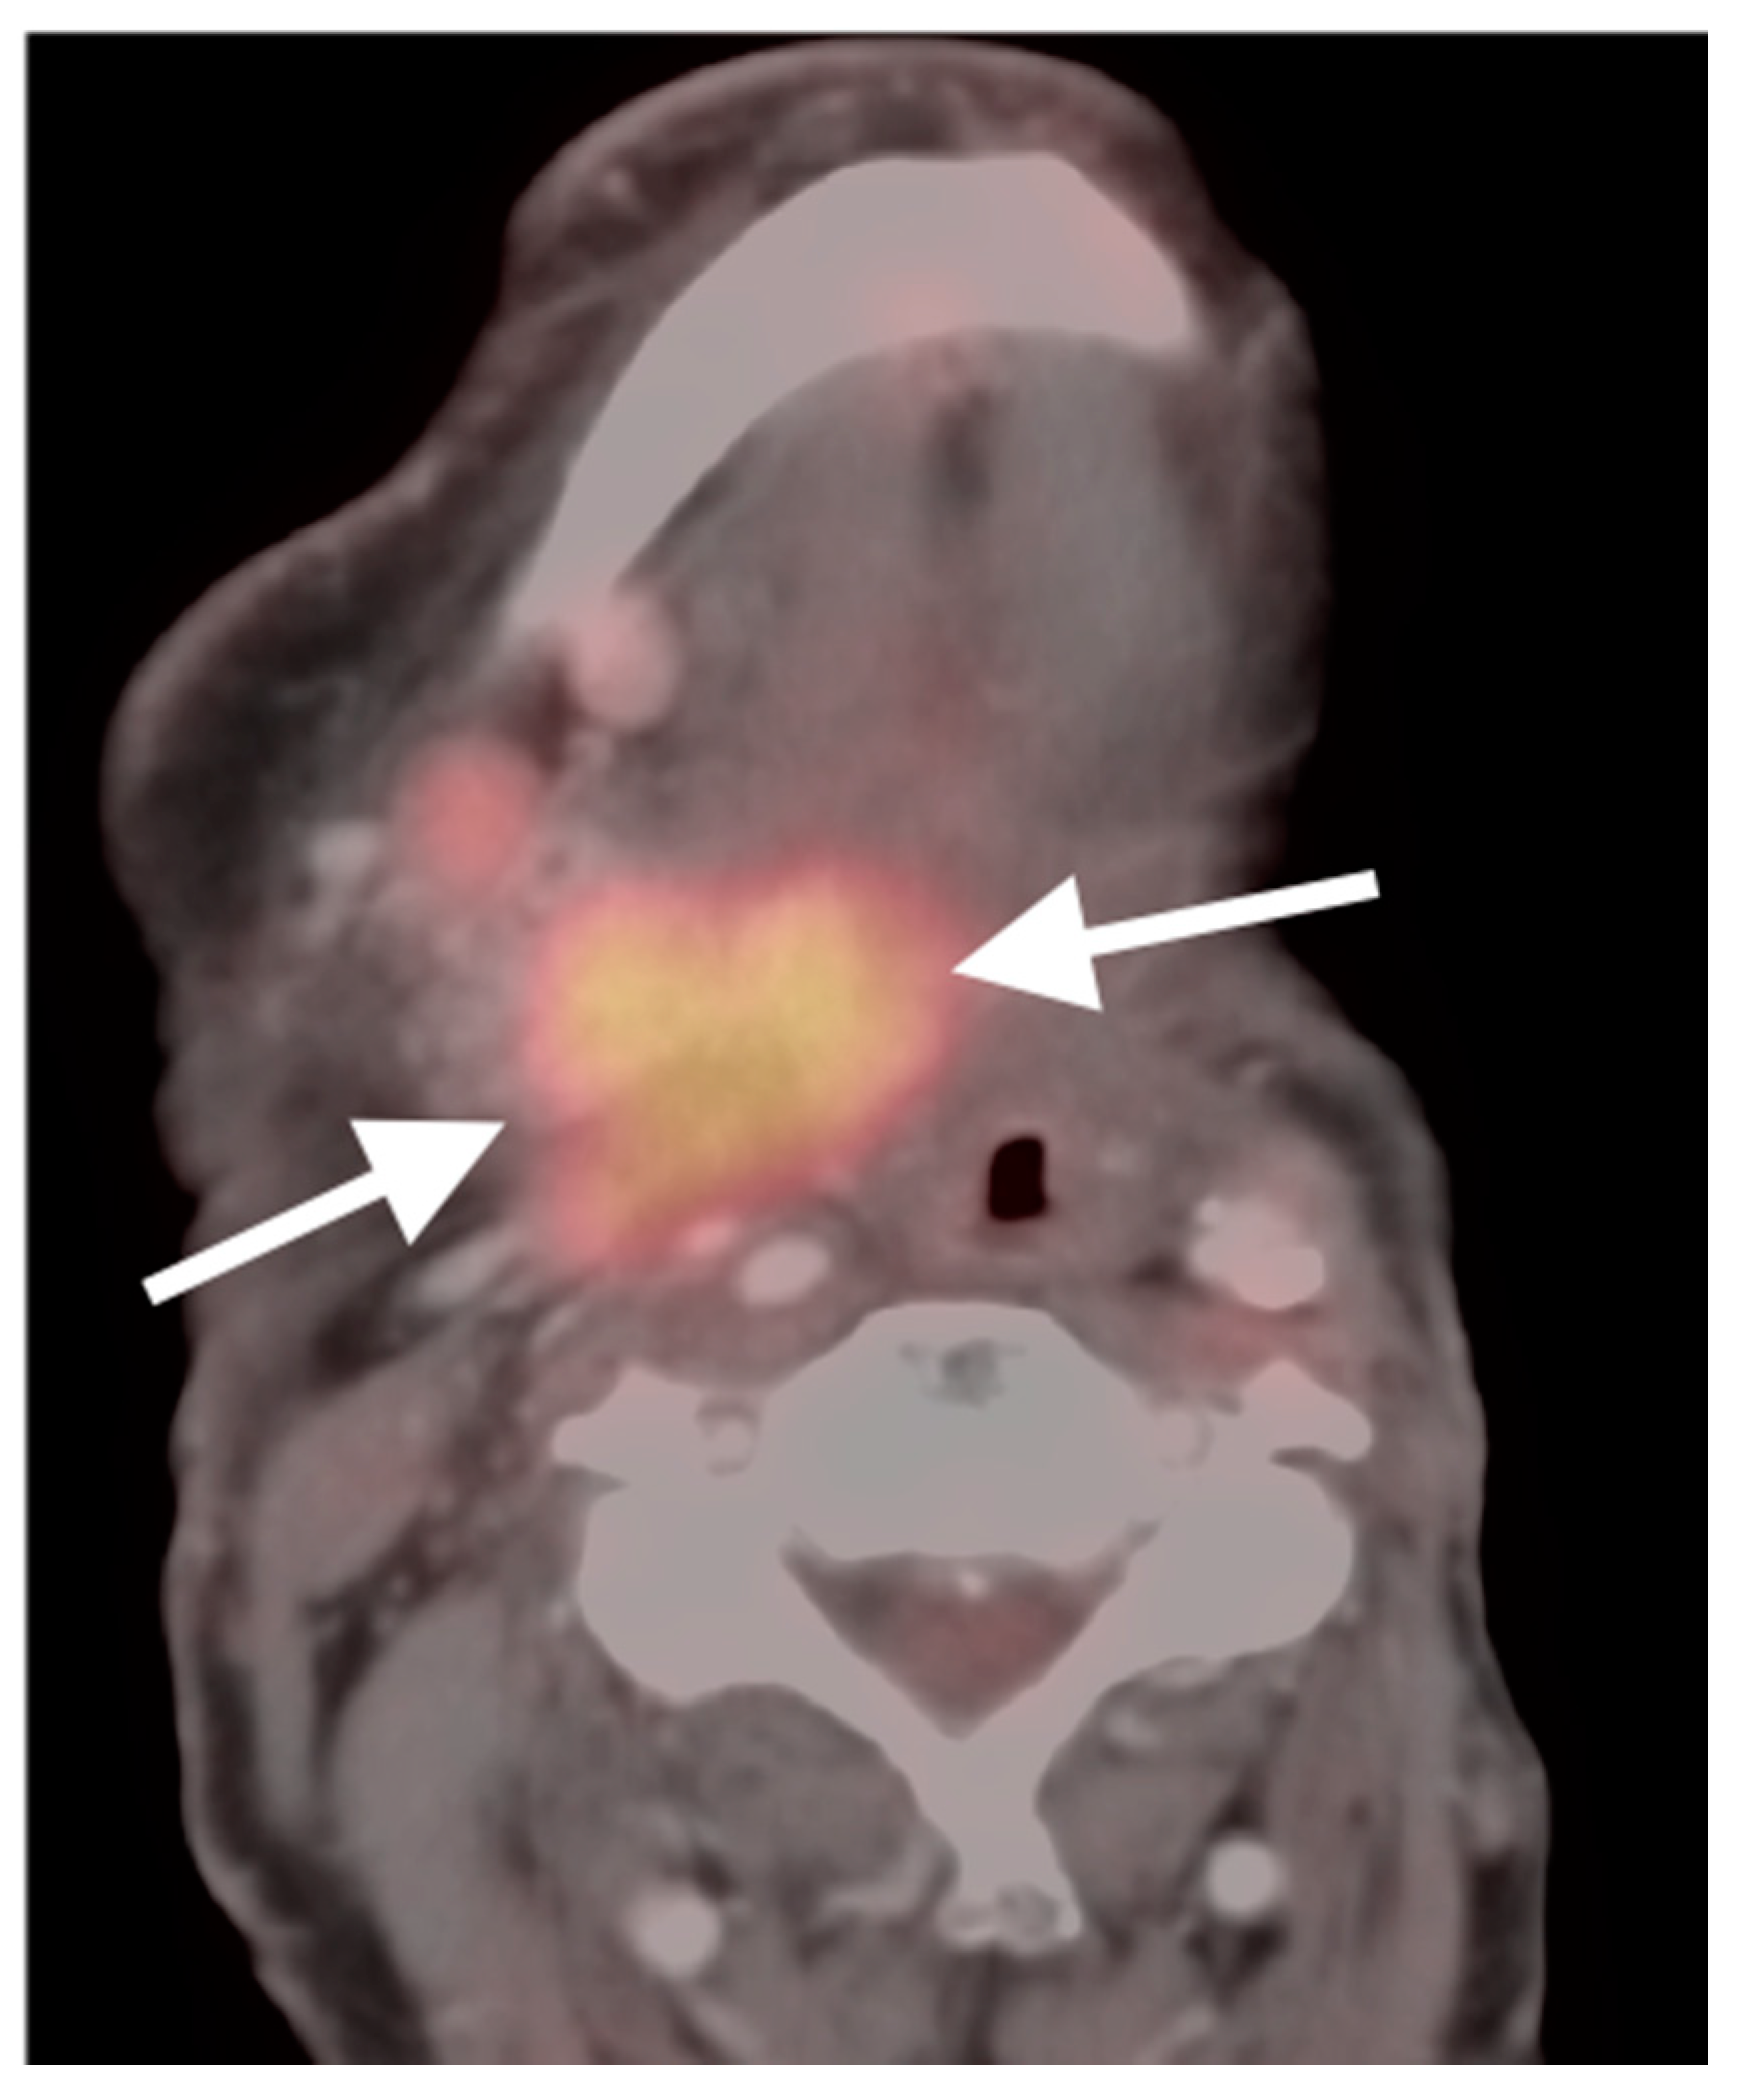

- Anaplastic thyroid cancer

- Bogsrud, T.V.; Karantanis, D.; Nathan, M.A.; Mullan, B.P.; Wiseman, G.A.; Kasperbauer, J.L.; Reading, C.C.; Hay, I.D.; Lowe, V.J. 18F-FDG PET in the management of patients with anaplastic thyroid carcinoma. Thyroid 2008, 18, 713–719. [Google Scholar] [CrossRef] [PubMed]